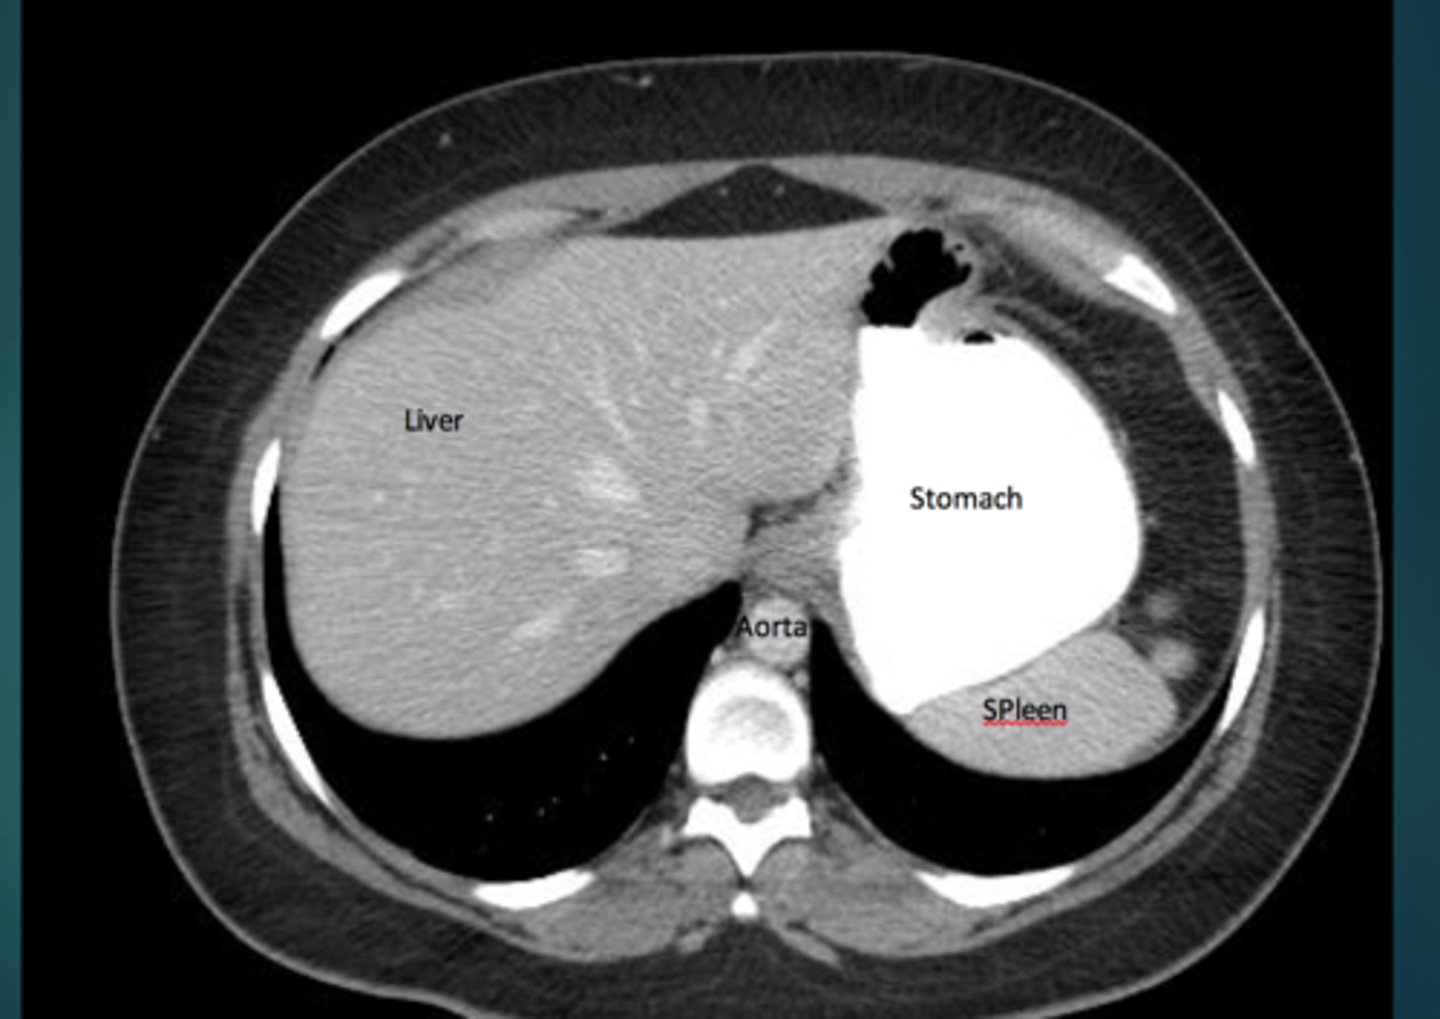

abdomen imaging

x-ray- pain, acute series, gas pattern, organs

CT- trauma, evaluate multiple organ systems simultaneously

US- gallbladder and biliary tree, female pelvis, AAA screening, POCUS trauma assessment

MRI- difficult diagnoses

liver

xray- only shows organomegaly

CT- most common method for imaging

ultrasounds- detecting size and ascites

MRI- define tumors

spleen

most highly vascular organ, most injured organ in blunt trauma

CT is diagnostic study of choice